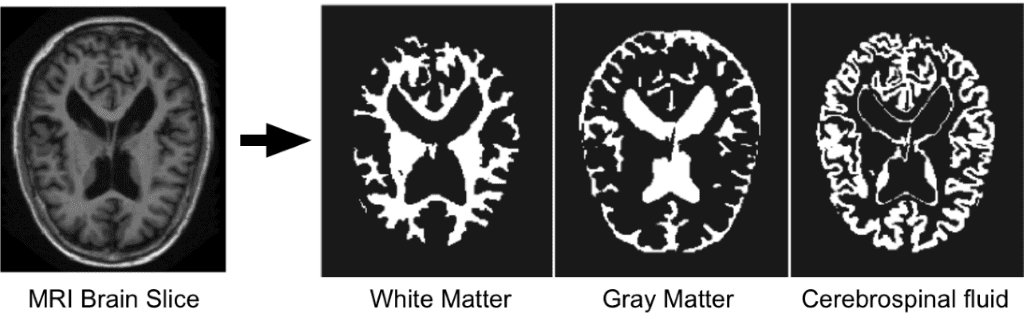

由于我们专注于大脑 MRI 自动分割,因此简要描述 DNN 试图区分的大脑基本结构很重要 a) 白质 (WM),b)灰质 (GM),c) 脑脊液 (CSF ) . 下图说明了脑 MRI 切片中的分割组织。

2017 年 I-Seg 医学影像数据挑战赛

在这个关键时期将婴儿大脑MRI 图像准确分割为白质 (WM)、灰质 (GM) 和脑脊液 (CSF),对于研究正常和异常的早期大脑发育都具有重要意义。生命的第一年是出生后人类大脑发育最活跃的阶段,伴随着快速的组织生长和广泛的认知和运动功能的发展。这个早期阶段对许多神经发育和神经精神疾病至关重要,例如精神分裂症和自闭症。这一关键时期越来越受到人们的关注。

该数据集旨在促进 6 个月婴儿脑部 MRI 的自动分割算法。本次挑战赛与MICCAI 2017联合举办,共有21支国际团队参赛。该数据集包含 10 个来自专家的密集注释图像和 13 个用于测试的图像。不提供测试标签,您只有在官网上传结果后才能看到您的分数。对于每个主题,都有一个 T1 加权和 T2 加权图像。